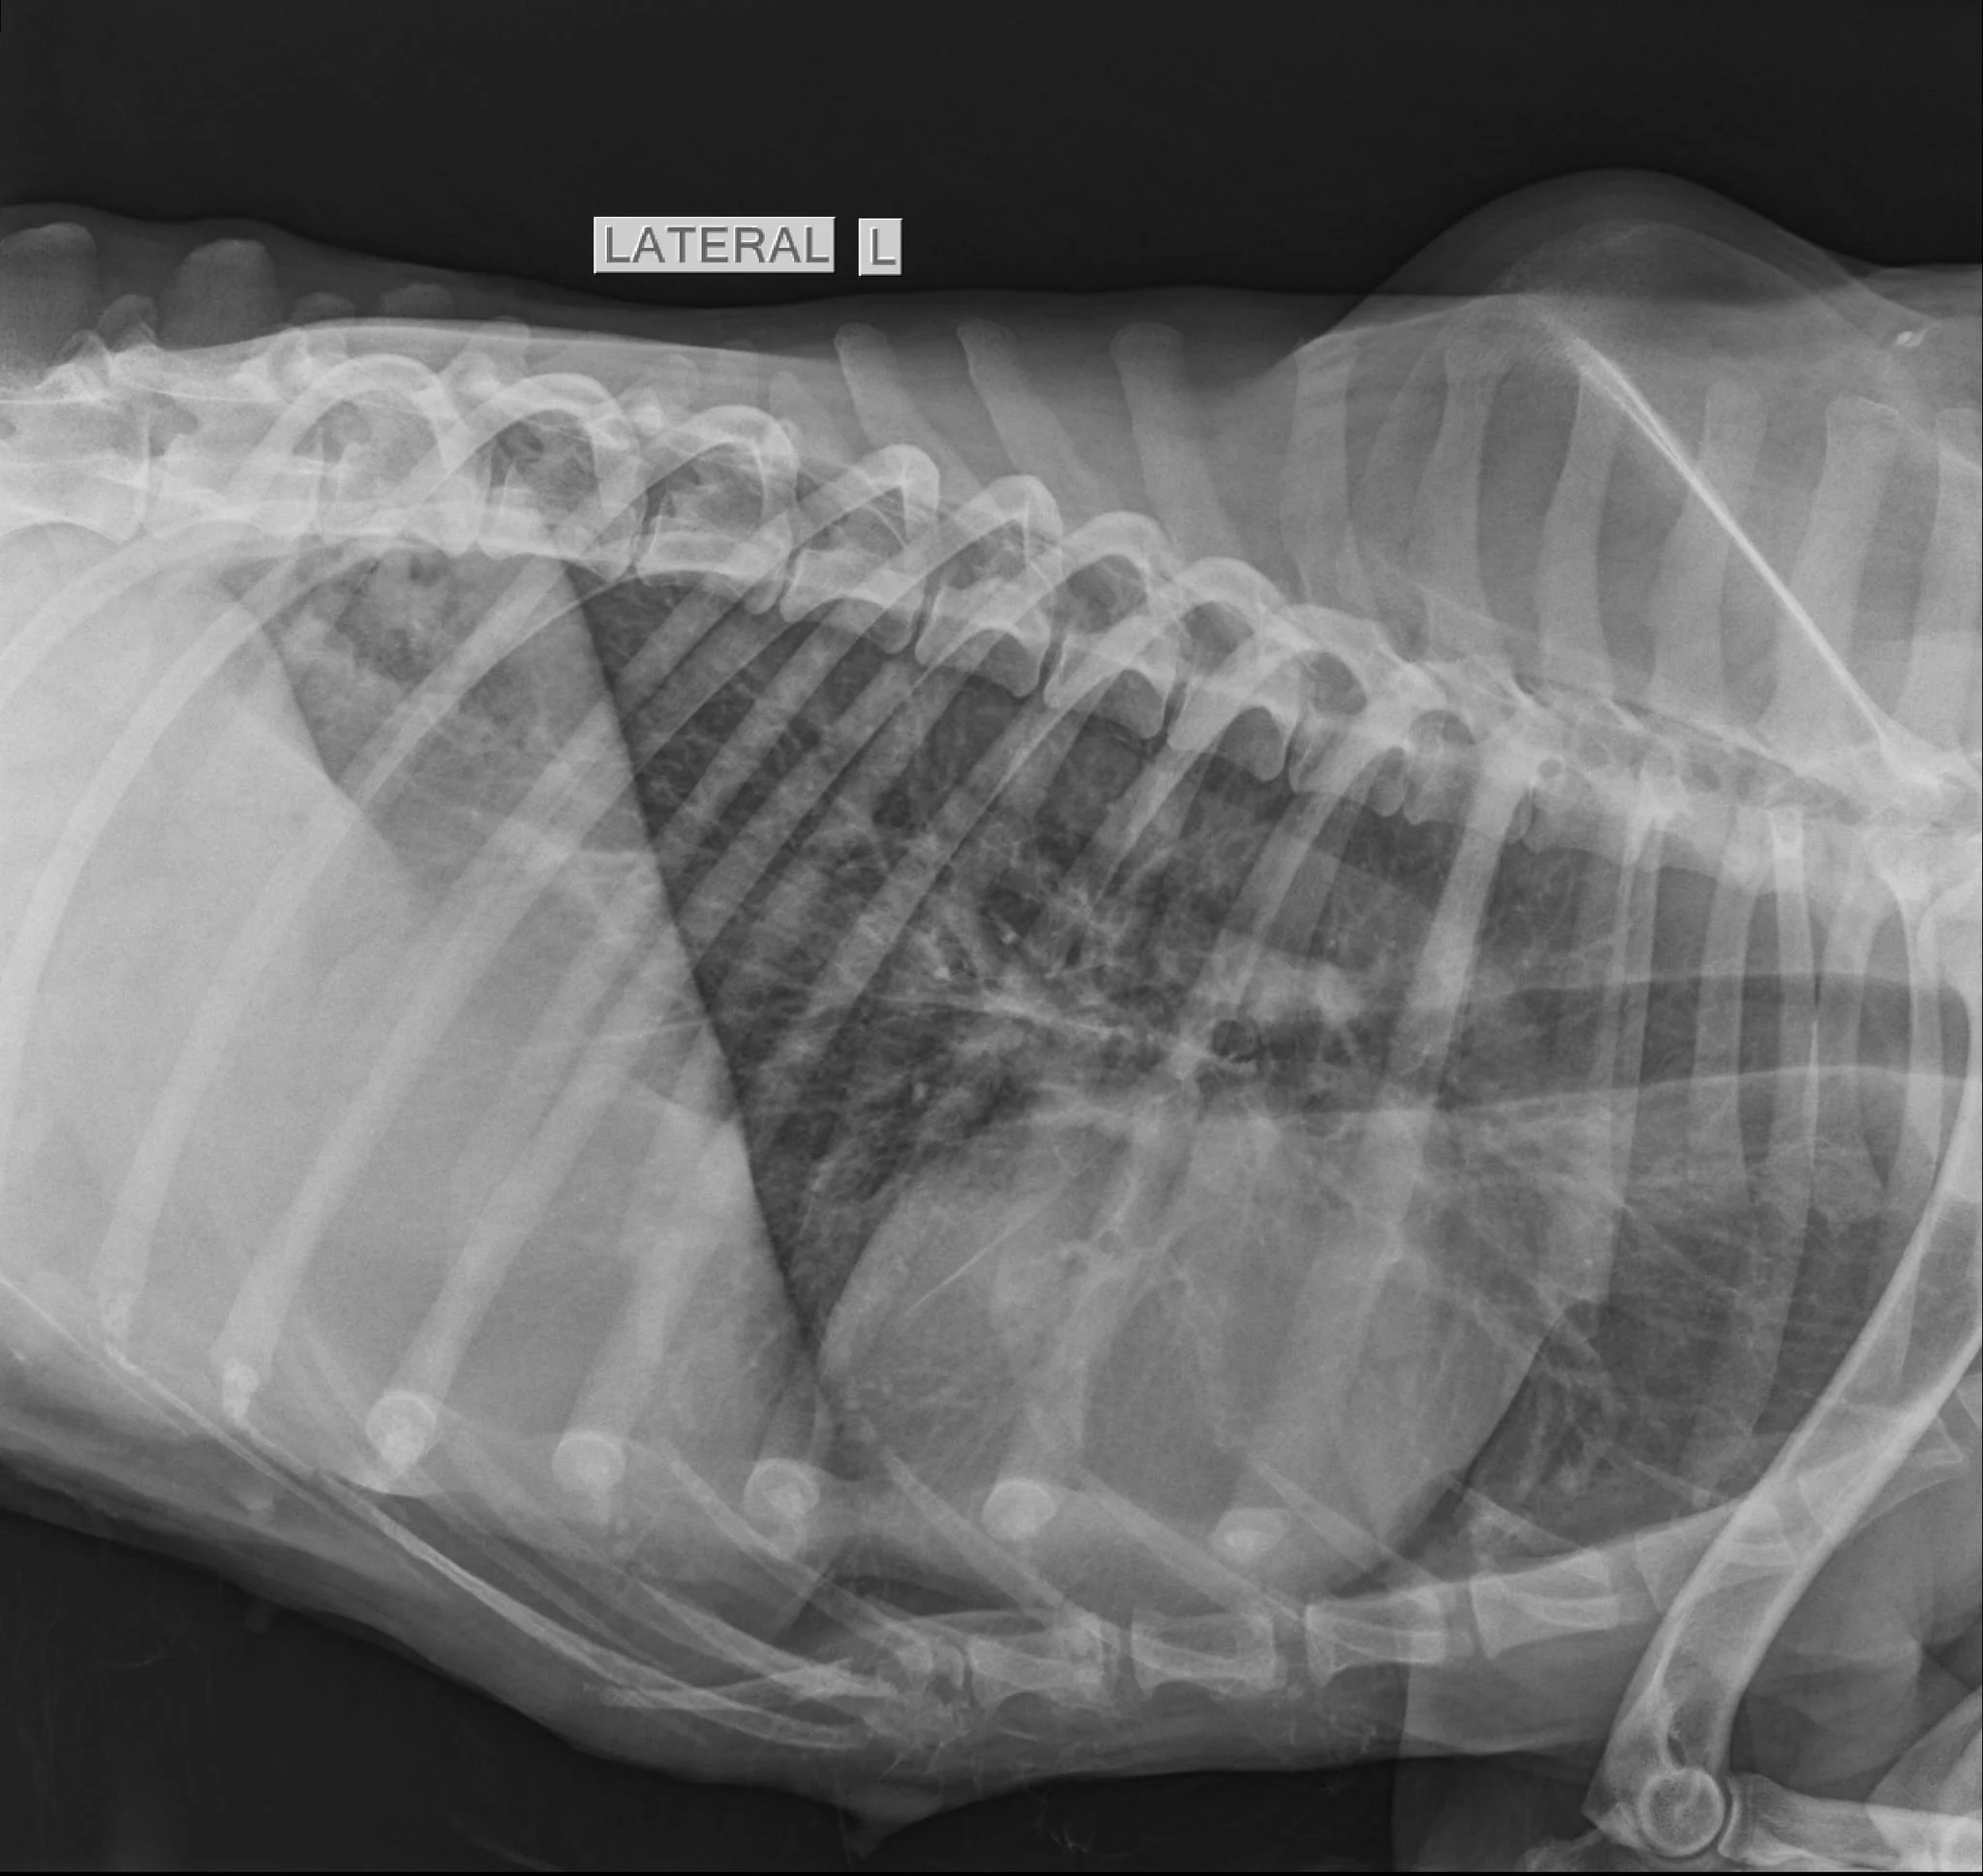

Radiologia este o parte esențială a medicinei veterinare moderne. Fie că este vorba despre un accident, o problemă digestivă, o durere apărută brusc sau o suspiciune de boală internă, radiografia ajută medicul să obțină rapid informații importante despre starea de sănătate a animăluțului tău.